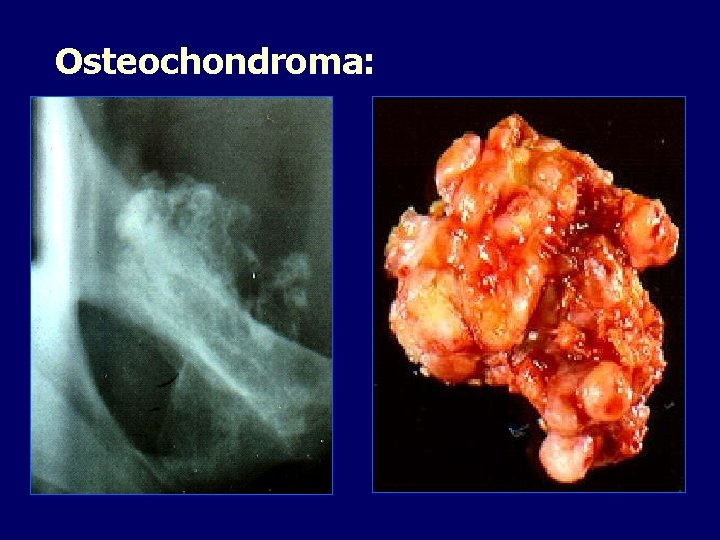

Osteochondroma:

Osteochondroma: